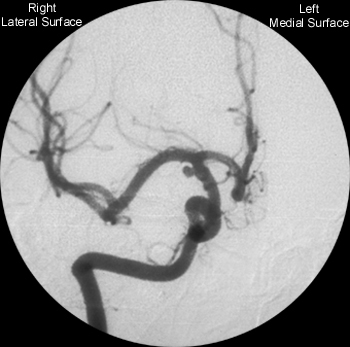

| Neurovascular Anatomy: Internal Carotid Artery: Angiogram |

Digital Subtraction Angiogram

Identify the following structures on the anterior-posterior angiogram of the internal carotid artery:

Second branch of supraclinoid internal carotid. Connects

Supplies

thalamus, hypothalamus, optic chiasm, and mamillary bodies.

Common

site for aneurysms -

AS IS SEEN IN THIS CASE |